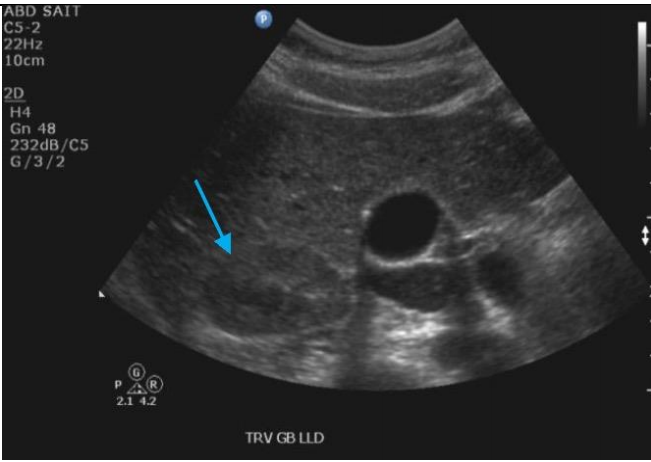

Label the blue, red, and yellow arrows

A

Blue: Right renal vein

Red arrow: IVC

Yellow: Gallbladder